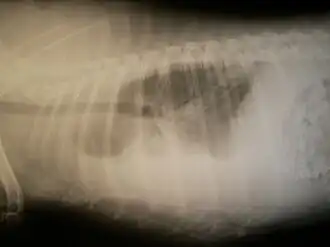

Radiographie

Une radiographie des poumons, de face et de profil, permet de faire le diagnostic en permettant de visualiser l'épanchement pleural.

Elle montre une opacité basale en nappe effaçant la coupole diaphragmatique et les culs de sac costo-diaphragmatiques.

Quand l'épanchement est très abondant, l'opacité recouvre tout l'hémithorax, refoule le médiastin du côté opposé. Quand il est peu abondant, l'opacité se limite à un comblement du cul-de-sac pleural inférieur.